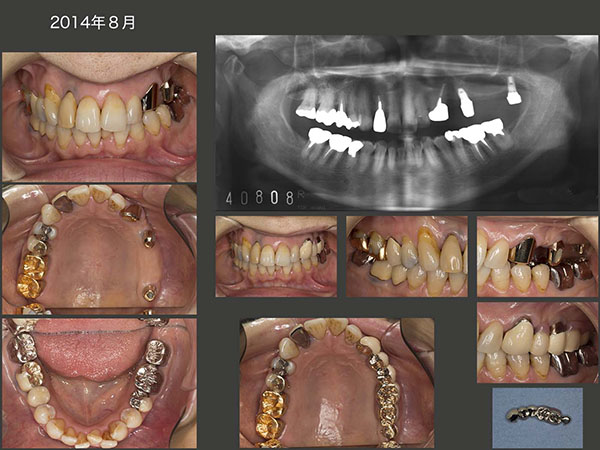

2004年6月初診,65歳男性.上顎前歯がグラグラするが主訴.下顎の骨隆起が著しく大きく,咬合力が強そうな感じ.咬合も低下してしまっている.このまま総義歯への流れに誘導する考えもあるが,本人は今ある歯をできる限り,残したいとのこと.右上2は歯周ポケットが根尖まで達しており保存できなかった.左上1〜3は歯周ポケットが最大8mmみられたが,歯周外科を行い5mm以下にすることができた.

2009年6月の状態.左上3の歯周ポケットが近心から口蓋にかけて10mmに増悪してしまった.パノラマX線写真とスライド中央右端に示す05年のデンタルX線写真を比較すると,09年は明らかに歯槽骨が吸収している.

歯が失活した可能性が否定できず,念のため無麻酔下にて舌側から穿通したところ,知覚があり,結局有髄のままであった.患者さんのブラッシングは大変良い.また左上1〜3は,中心咬合位では咬合しないように配慮し(結果的に間違いであったが),また,ここで食事をとらないようにお願いし,さらに,3歯を連結固定することで咬合力に対抗したことから,結局この歯槽骨の吸収の大きな要因は,よくわからない.しかし,何らかの大きな力が加わっているのであろうと推測している.

以前,私は咬合低下症例の義歯製作にあたって,わざと義歯の咬合を少し高くして,前歯に力が加わらないようにしていたことがある.しかし,今はこの考え方を否定している.前歯で力を感じ,この刺激が脳に伝わり,その結果咬合力が抑制されるという考え方がある.また,咬合を挙上すると,咬合力自体が増大してしまうという説がある.そして,数年経って残存歯あるいは顎堤を破壊し,咬合を挙上する前の位置に結局戻ってしまう.この症例も義歯装着時において,義歯の臼歯部のかみ合わせを若干高くし,前歯が当たらないように製作してしまったが,09年6月の時点で,左上1〜3の前歯がしっかり咬合するところまで義歯の咬合調整を行い,咬合を低くした.その結果,左上1に掛かっていたレストがほぼなくなってしまった.

この先,このまま経過を観察し,いつか総義歯にもっていくか,あるいはここで積極的に介入し,総義歯にならないようにするか否かを患者さんに問うたが,患者さんは後者の気持ちが強かった.そこで,インプラントを2本植立する治療計画を立案した.

2012年2月,右側でも咬めるようになったためか,ブリッジの支台歯である右下5にセメントアウトが生じた.片側脱離であったが,ブリッジ全部を除去する羽目になった.右下5は矯正的挺出を行い,歯肉縁上歯質を確保した.もう一回,固定式のブリッジの装着も可能であるが,またセメントアウトが生じる危険があること,あるいは歯根破折が生じた時の対応がしやすいことから,可撤式であるコーヌス義歯を装着した.

インプラントを装着したことで,左上1〜3に加わる力は減少したと思い,13年7月,左上3の歯周外科を再度行ってみた.しかし,残念ながら歯周ポケットの改善には至らなかった.